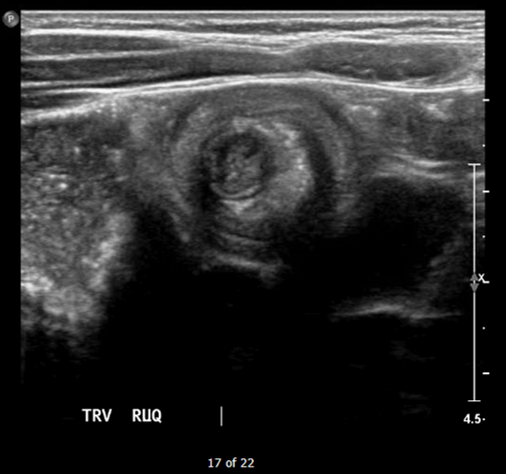

The patient’s abdominal ultrasound revealed intussusception in the right upper abdominal quadrant. The transverse ultrasound view showed a “doughnut sign” (dashed yellow line), telescoping bowel (yellow arrow), and invaginated hyperechoic mesenteric fat with crescent configuration (dashed orange line). The sagittal ultrasound view demonstrated the intussusception formed by the outer recipient bowel loop (yellow arrows), invaginated hyperechoic mesenteric fat (orange asterisks), and telescoping bowel centrally (red arrow).

Ultrasonography should be the initial imaging modality in cases with clinical suspicion for intussusception.4 Previously, contrast enemas were often used as a diagnostic tool and treatment modality. Studies have demonstrated that the modality choice had been related to age, with infants less than six months more likely to undergo enema while children greater than four were more likely to have a computed tomography scan or ultrasound.5 In the pediatric population, ultrasound has a sensitivity of 97.9% and specificity of 97.8% for diagnosis of ileocolic intussusception.6 A “doughnut,” “pseudokidney,” or “target sign” are diagnostic findings.3,7 The study could be performed by radiology or at the bedside in the ED.8,9 A study reported that with limited training, ED physicians could accurately perform ultrasound to diagnose intussusception, with a sensitivity of 85% and a specificity of 97%. Further studies are needed to determine the utility of bedside ultrasound for the diagnosis of intussusception in the community setting.3